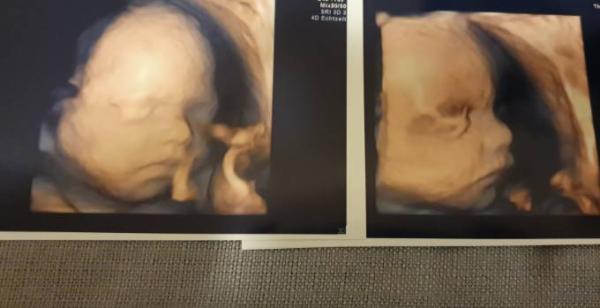

...heute war der Termin im KH zum 3D Babykino. Soooo toll!! Unser Mädchen (wurde noch mal bestätigt) soll nun schon fast 800g wiegen - wahnsinn. Und ich bin echt hin und weg von den Bildern..wie hübsch sie ist. Anfangs hatte ich Angst das es gruselig aussieht..aber keinesfalls!! Kann es nun kaum abwarten bis sie kommt. Der Chefarzt sagte das wir noch mal zur Geburtsplanung im Februar drüber sprechen ob wir evtl die Geburt 1 Woche vor Termin anstupsen damit ich zierliche Frau nicht wieder so einen Brummer bekomme. Ich bin echt froh das er das auch so sieht..die beiden Jungs wurden auch eingeleitet (nach und zum Termin) und es hat trotz geburtsunreifem Befund direkt geklappt und sie waren innerhalb weniger Stunden da. Aber ich will die Hoffnung nicht aufgeben das es diesmal von selbst los geht!

Bild zu Zurück vom 3D - Schockverliebt - Forum für April - Mamis

Ein sehr schönes Foto. Freut mich, dass du so einen schönen Termin hattest...